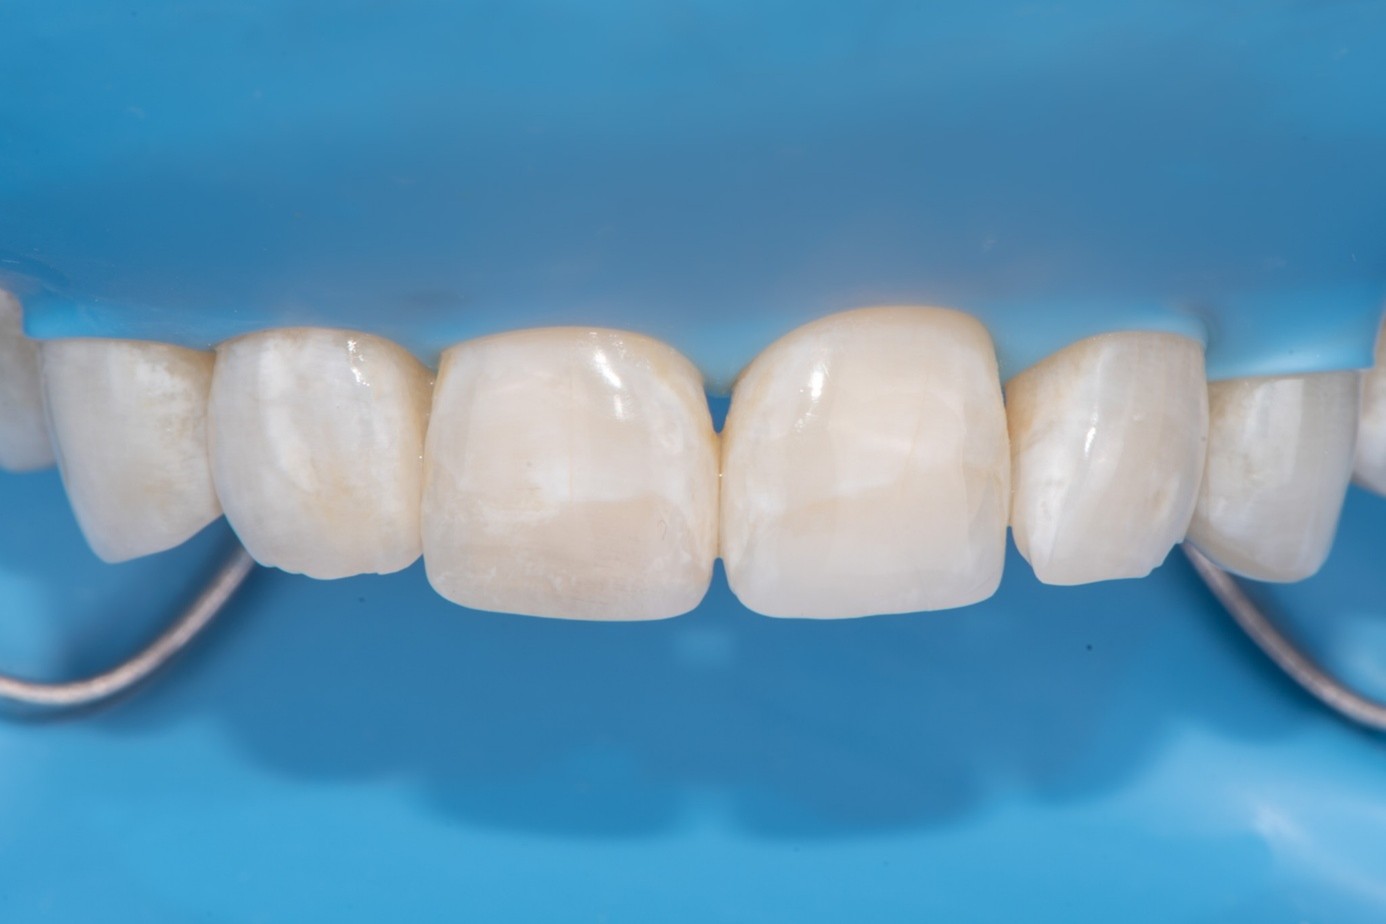

Before light-curing, flowable composite resin was placed in the cavity, and the fractured segment was repositioned precisely into its original location. Heated packable composite was avoided due to thinness and brittleness of the fractured piece. Excess bonding and composite were carefully removed using a microbrush. The restoration was then polymerized from multiple directions to ensure optimal cure (Figure 25 and Figure 26). Finally, the restoration was polished and contoured to blend seamlessly with the surrounding tooth structure and adjacent composite (Figure 27).

(25.) Correction and removal of composite excess, followed by light polymerization.

Figure 25

(26.) Correction and removal of composite excess, followed by light polymerization.

Figure 26

(27.) Final intraoral view after complete polymerization under glycerin gel, showing a seamless repair with invisible margins, making the fracture line undetectable.

Figure 27